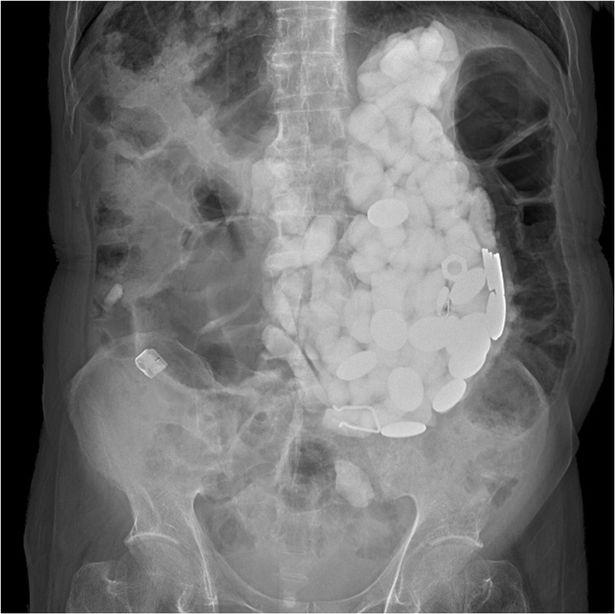

Simptomele i-au determinat pe medici să îi facă o radiografie și astfel a ieșit la iveală că omul are corpuri străine în corp și că trebuie urgent operat.

Rând pe rând, chirurgii au scos aproximativ două kilograme de pietre și capace de la sticle!